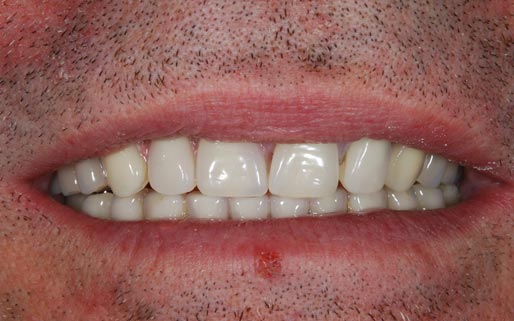

Con protesi fissa superiore e protesi fissa inferiore

I denti irrecuperabili dell'arcata superiore ed inferiore del paziente di anni 65

sono stati sostituiti da 10 impianti, cioè protesi radicolari endo-ossee che sostengono le protesi fisse superiore ed inferiore.